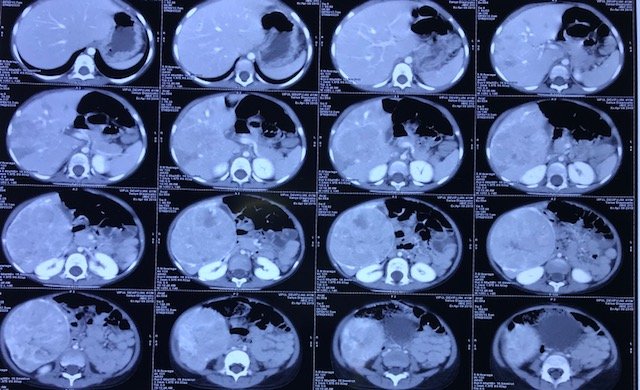

CT Scan of Abdomen showing Large Liver Tumor arising rom right lobe of Liver

X-rays, sonography of abdomen, contrast CT scan(abdomen& chest) and/or MRI with angiography are the imaging studies required to know the extent of the disease and resectability (safe removal) of the tumor.